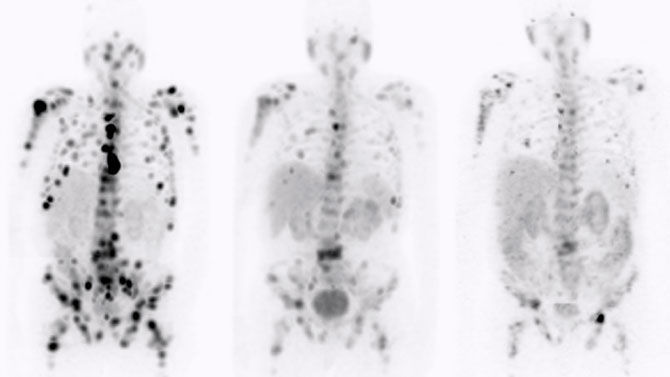

The approach of zeroing in on tumor receptors with positron- and gamma-emitting radioligands to visualize cancer cells, and beta- or alpha-emitting radioligands to destroy cancer cells makes theranostics the quintessential targeted care pathway.

Radioligand therapies have historically been one of the last treatments for cancer, but new evidence shows positive results if this type of care is used earlier, closer to when cancer is diagnosed.² Because of the limited side effects of this precision treatment, it is now a pre-chemo therapy option for some patients.

Already chosen to treat patients with mCRPC, neuroendocrine tumors, thyroid and other cancers, researchers are exploring⁵ a wider range of cancers, such as brain, breast, pancreatic, and ovarian, that may be treatable with radioligand therapies in the next five to ten years.

Radionuclides like ¹⁷⁷Lu, ¹³¹I, and ⁹⁰Y have established themselves as effective cancer treatments.⁶ In the next few years, researchers are working to add several more radionuclides to the fight against cancers, including two alpha-emitting candidates, ²¹²Pb and ²²⁵Ac.⁵